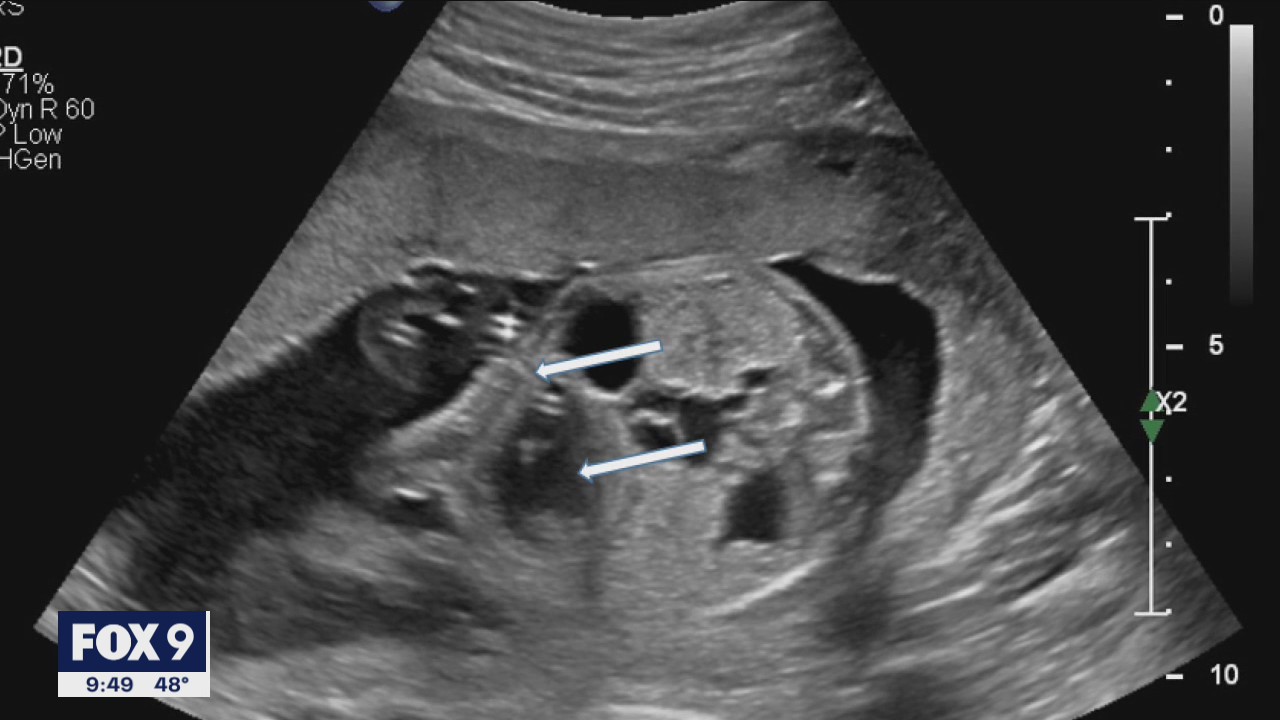

St. Paul family welcomes healthy baby boy after successful in utero surgery

A rare discovery on a St. Paul mother?s 20-week ultrasound forced a family to make the tough decision for their baby to undergo surgery in utero.